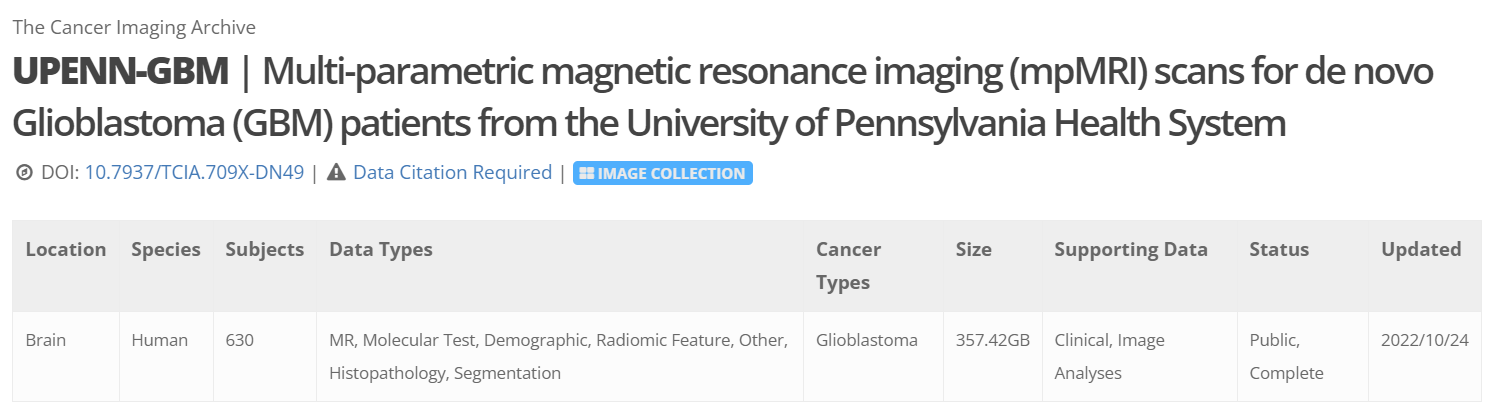

数据采集 protocol(dicom header)